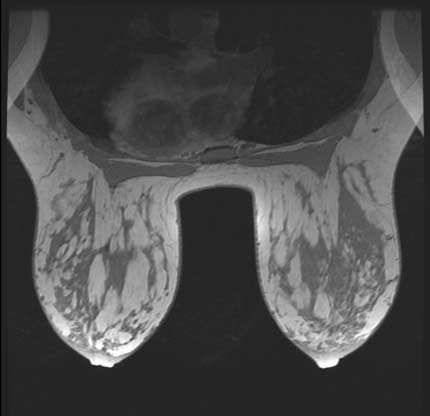

Imagen de RMN de alta resolución de ambos senos provee detalle anatómico.

Nota: Las imágenes se muestra para fines ilustrativos. No trate de sacar conclusiones comparando esta imagen con otras en el sitio. Solamente los radiólogos calificados deben interpretar las imágenes.